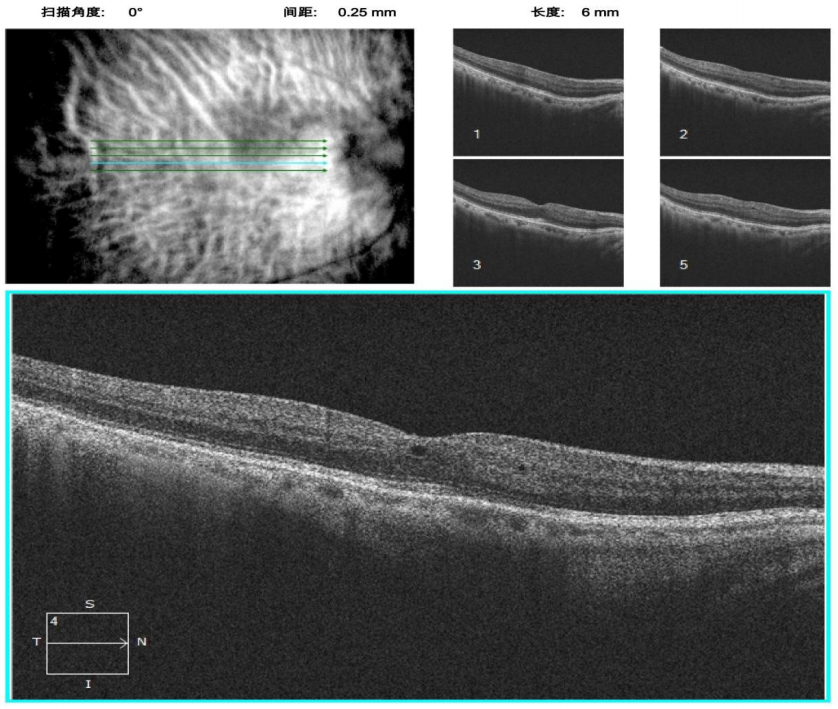

治疗:入院后在局部麻醉下行右眼囊袋拉钩固定下超声乳化+IOL悬吊+前段玻璃体切割术,手术顺利,术后予以左氧氟沙星滴眼液、百利特滴眼液、普拉洛芬滴眼液,每日4次抗感染治疗,术后第一天术眼裸眼视力0.10,矫正-2.00 DS = 0.20,眼压:12 mmHg,角膜透明,前房深浅可,IOL位正。右眼术后1个月患者为行左眼晶状体不全脱位及白内障手术入院,光学相干光断层扫描(OCT)检查示:右眼黄斑区形态改变,中心凹隆起,提示右眼黄斑区囊样水肿(图3)。诊断:右眼人工晶状体植入术后、右眼黄斑水肿。予以复方平地木颗粒口服,溴芬酸钠滴眼液滴眼。2周后复诊视力明显好转,右眼裸眼视力0.40,矫正-3.00 DS/-1.00DC×40 = 0.80,眼压:16 mmHg。黄斑区水肿明显好转。OCT检查示:右眼中心凹局灶色素上皮增厚,可见少许微囊样水肿(见图四)。

图3 右眼术后 1 个月黄斑区形态改变,中心凹隆起,呈囊样水肿改变,提示右眼黄斑区囊样水肿

Figure 3 One month after operation, the morphology of the macular area changed, the central fovea bulged and showed cystic edema, suggesting cystoid macular edema in the right eye

图 4 右眼术后黄斑水肿药物治疗 2 周后,OCT 示右眼中心凹局灶色素上皮增厚,可见微囊样水肿

Figure 4 After two weeks of drug treatment for postoperative macular edema, the OCT of the right eye showed focal pigment epithelium thickening and microcystic edema in macular fovea